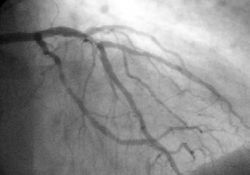

Angiography

Angiogram of the coronary arteries.